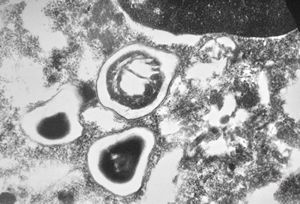

M,10y. | herpes virus - herpetic encephalitis